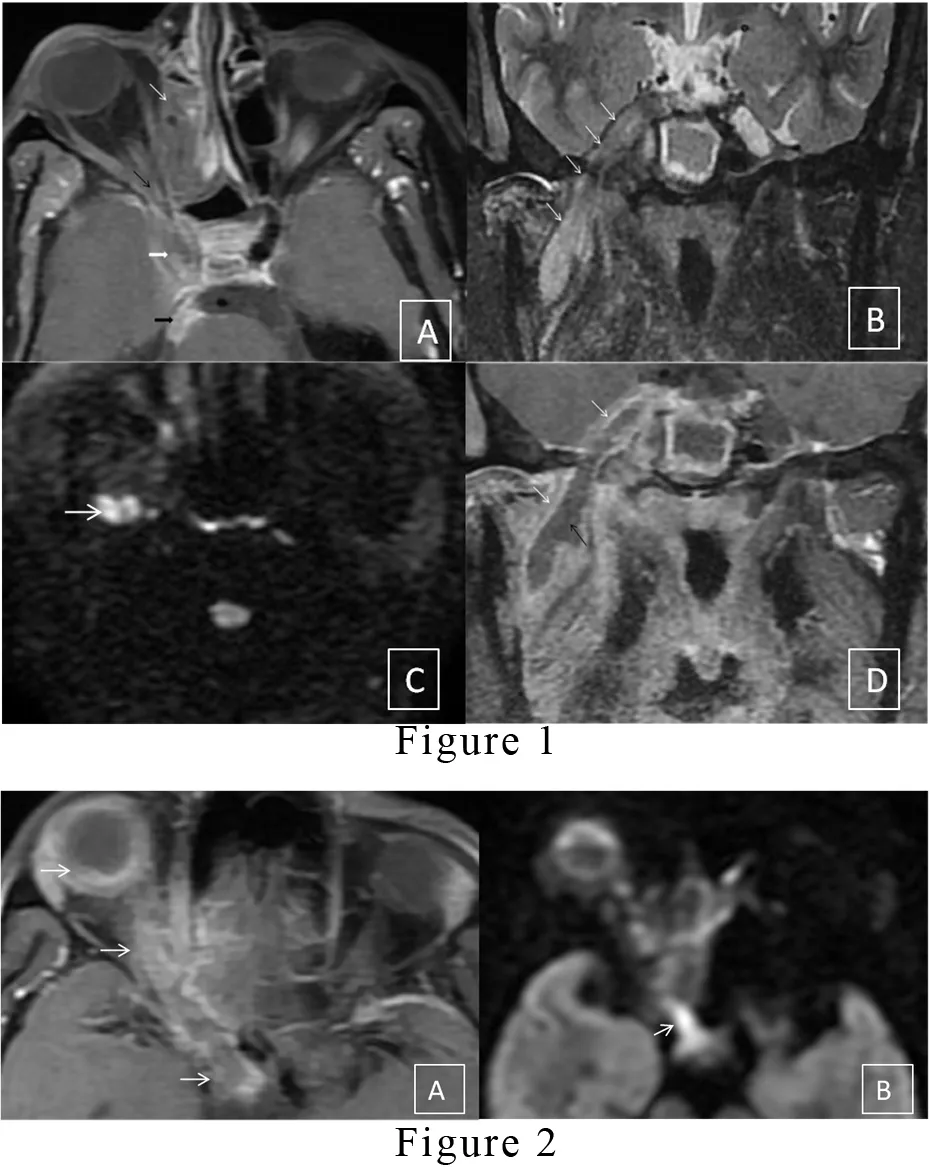

Perineural extension of fungal infection is a rare complication observed in post-Covid-19 immunocompetent mucormycosis patients during this pandemic. Rhino-orbito-cerebral mucormycosis is an opportunistic fungal infection caused by members of family mucoraceae. Mucormycosis proved to be the lethal disease in untreated diabetic or patients on immunosuppressive therapy with the same pattern of spread and severity. [1,2] Rhino-orbito-cerebral mucormycosis has been declared endemic by the Indian government recently. Due to the aggressive pattern of spreading in this disease, it rapidly involves the surrounding structures. Cerebral extension of the organism occurs either by direct extension, hematogenous route or perineural spread. Over two months, we have observed nine patients with perineural spread involving cranial nerves during this endemic. The peculiar imaging findings in a perineural spread include thickened nerves with abnormal enhancement and perineural fat stranding. Initially, the enhancement in the affected nerve represents neuritis. However, it can progress into a full-blown abscess. The trigeminal nerve is a large cranial nerve with a unique course that enables us to easily demonstrate this evolution line. Magnetic resonance imaging (MRI) stands to be the best diagnostic and non-invasive imaging technology that produces three-dimensional detailed anatomical images that help determine disease spreading with treatment.[1] This article highlights the role of MRI in the diagnosis of perineural complications observed in rhino-orbito-cerebral mucormycosis. Here, we present two representative cases of a 55-year-old female and a 60-year-old male who presented to our hospital with facial pain, facial numbness and high-grade fever. On initial examination, periorbital soft tissue swelling and facial redness were found with a history of hospitalization for Covid-19 pneumonitis in the recent past. The patients were administered steroids during the previous hospital stay. On relevant laboratory investigations, both the patients had deranged blood glucose levels. The patients underwent an MRI of paranasal sinuses and brain, revealing orbital cellulitis, pansinusitis, abnormal signals in the premaxillary skin, retro-antral fat and masticator space extending to the right cavernous sinus [Figure1 A]. The inferior turbinates and paranasal sinuses also had non-enhancing areas on post-contrast MRI, representing necrosis. In the first patient, the mandibular division of the right trigeminal nerve was thickened and showed heterogeneous signals on all MRI sequences [Figure 1B]. The Diffusion-weighted image (DWI) image shows diffusion restriction in the abscess in the nerve [Figure 1C]. On post-contrast, T1 fat-suppressed images, the nerve reveals peripheral enhancement with central liquefied non enhancing collection, represent an abscess [Figure 1D]. In another similar patient, there is the involvement of the pre septal soft tissue, eye globe and optic nerve up to the optic chiasma on the right side was observed[Figure 2A], and the path of spread is seen extending along the optic nerve on a diffusion-weighted image[Figure 2B]. There are very few documented cases available in the literature describing the perineural spread of fungal infection, especially after this Covid era; however, similar cases have been reported previously in uncontrolled diabetic patients by Bruno Galletti et al.[1] A surgical biopsy from the inferior turbinate was done, which revealed non-septate fungal hyphae. Both the patients managed with anti-fungal drugs; however, they did not improve much. Both the patients are receiving treatment in our hospital till the writing of this article.

• Figure 1: (A) T1 weighted fat-saturated (T1W FS) post-contrast, axial image show shows Heterogenous enhancement in the right ethmoid sinus (white arrow), orbital apex (black arrow), extending to right cavernous sinus (thick white arrow) and then till fifth nerve nucleus (thick black arrow). (B) Short tau inversion recovery (STIR) image in the coronal plane shows Abnormally increased signals along the right mandibular nerve (white arrows). (C) Diffusion-weighted image (DWI) in the axial plane depicts restricted diffusion in the mandibular nerve (white arrow). (D)T1 weighted fat, saturated post-contrast image in coronal plane demonstrates Peripheral enhancement (white arrows) with central liquefied non-enhancing collection (black arrow) along mandibular nerve passing through foramen ovale.

• Figure 2: (A) T1 weighted fat-saturated (T1W FS) post-contrast, axial image show contiguous involvement of the pre septal soft tissue, eye globe and optic nerve up to the optic chiasma on the right side (white arrow). (B)The path of spread can also be evaluated on a diffusion-weighted image(White arrow).